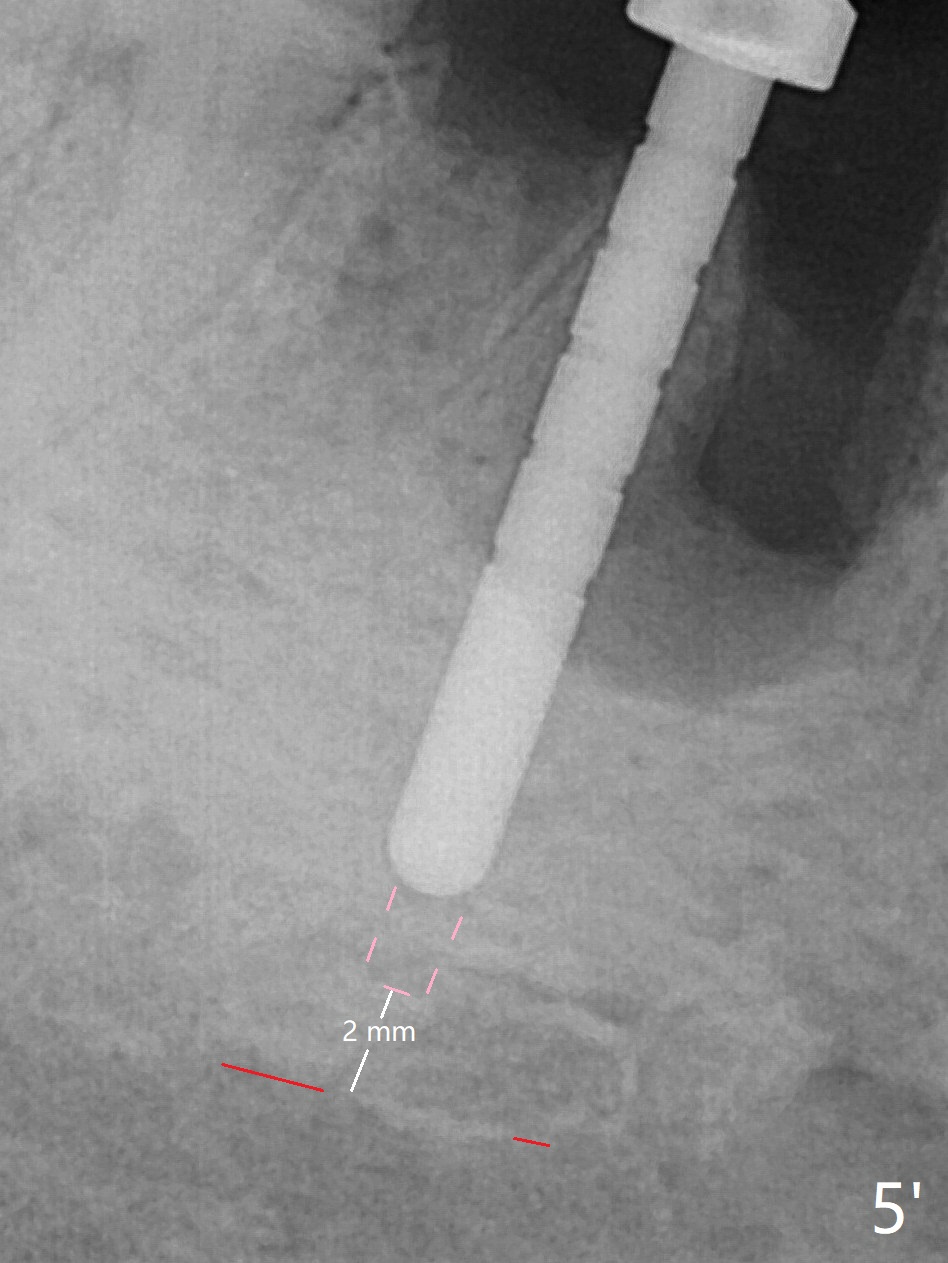

Preop oral Amoxicillin seems to be associated with reduction in the buccal and lingual (Fig.3 arrow) fistulae at #30, but there is mesiobuccal swelling (Fig.1 *) with 7 mm pocket (Fig.2). Osteotomy is initiated in the middle of the septum (Fig.3-5 S). As the osteotomy increases, it shifts mesially (Fig.6 arrow). Guided surgery is able to reduce shifting. A 5x13 mm implant is not seated completely (Fig.7) apparently due to osteotomy shifting. After removal of the bone from the osteotomy distally, the implant remains unseated with lower torque value (Fig.8). Following reuse of the 4.3 mm drill deeper by 1-2 mm, the implant is seated to a satisfactory depth (Fig.9 with increase in torque to 50 Ncm) with placement of Vera Graft (*) and a 7.5x4(3) mm abutment. After a second round of allograft placement (Fig.10 *), the implant is found to be 4 mm from the IAC. At the later stage of osteotomy, the coronal end of the septum is destroyed with loss of osteotomy depth landmark. It is apparent that the soft tissue landmark may be more reliable. The implant threads appear to be covered by the bone graft 3.5 months postop (Fig.11). The abutment is changed to 6.5x5(3) mm one before impression with minor margin prep. The bone density seems to increase 5 months postop, i.e., immediately post cementation (Fig.12) and 10 months postop (5 months post cementation (after retightening abutment), Fig.13 (*)). Periimplantitis develops mesiobuccally, consistent with bone loss 1 year 7 months post cementation (Fig.14 *); the implant seems to have been buccally placed. Bone graft is necessary with PRF or GEM21S if the vein is small and 6-month membrane with a hole around a 7.5x4(4) cemented abutment for easy wound closure. Take 5x5 CM CBCT to determine which wall has defect, buccal or lingual. Check mesial contact. If so, remove the crown, reseat the abutment (possible incomplete seating) and re-impress after bone graft.